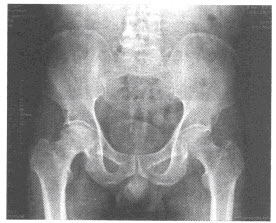

124、单项选择题

男,根据其正常骨盆影像图像,判断其最可能的年龄()

A.2岁左右

B.8岁左右

C.6岁左右

D.12岁左右

E.10岁左右